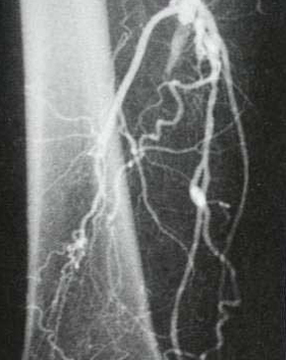

Verschluss der Oberschenkelarterie